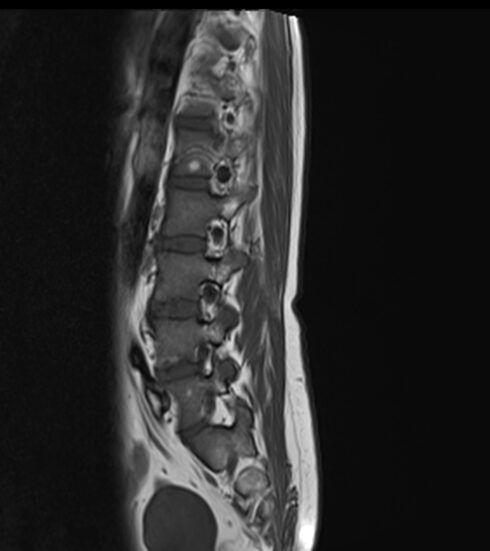

Resonancia Magnética de columna lumbar

“QUISTES PERINEURALES”

Los quistes perineurales son quistes llenos de líquido cefalorraquídeo en las raíces nerviosas, localizados principalmente en la zona sacra de la columna vertebral, aunque pueden encontrarse en cualquier sección de la columna vertebral; pueden causar una radiculopatía progresivamente dolorosa. Las mujeres se ven afectadas con mayor frecuencia que los hombres. Los pacientes con quistes perineurales presentan dolor en la zona de los nervios afectados por el quiste, debilidad muscular, dificultad para sentarse durante periodos prolongados, pérdida de la sensibilidad, pérdida de reflejos, dolor al estornudar o toser, inflamación en la zona sacra, parestesias, dolor de cabeza, ciática, y disfunción intestinal, de vejiga y sexual.

El diagnóstico se basa en la resonancia magnética.